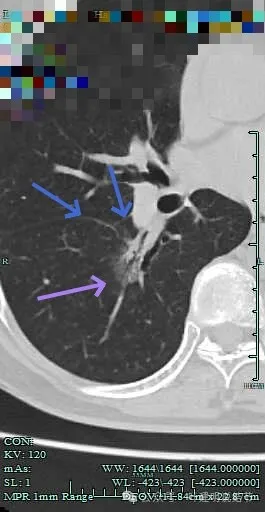

边缘区也不光滑,显毛糙。

靶重建显示混合密度,边缘毛糙,内部杂乱,灶内支气管通气且僵硬。

病灶影响到斜裂肺门部,边缘毛刺明显。灶内支气管僵硬。

杂乱密度,整体轮廓较清,边缘毛糙。

斜裂根部有增厚并与病灶连着。考虑是肿瘤已经侵及叶间裂。